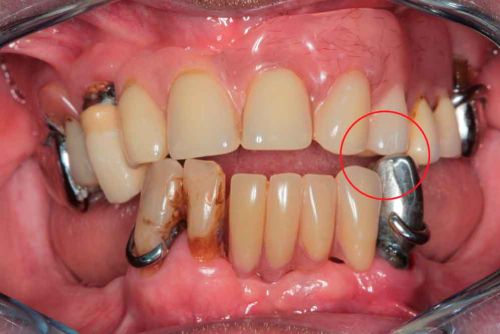

Situation initiale

Situation

Patient de 66 ans. Souhaite retrouver un confort fonctionnel et améliorer l'esthétique.

Plaintes

- Manque de stabilité de ses prothèses amovibles

- Difficultés à manger

- Affaissement de la lèvre supérieure

Plan de traitement

Les structures parodontales des dents restantes ne sont plus suffisantes. Une édentation est envisagée. Le plan de traitement est orienté vers une prothèse complète maxillaire amovible et une prothèse complète mandibulaire supportée par des implants. Le défi est de passer de la situation initiale aux provisoires en utilisant les données du patient.

Photo - Situation intra-orale